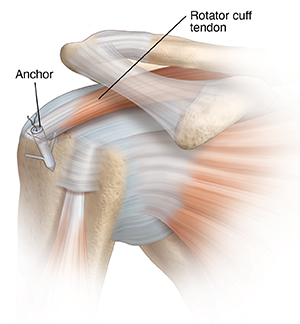

Torn rotator cuff

The rotator cuff can tear due to a sudden injury or from overuse. This can cause pain, weakness, and loss of normal shoulder movement.

During surgery, torn rotator cuff tendons may be trimmed. The tendons are then reattached to the humerus. This is done with stitches, anchors, or surgical tacks.